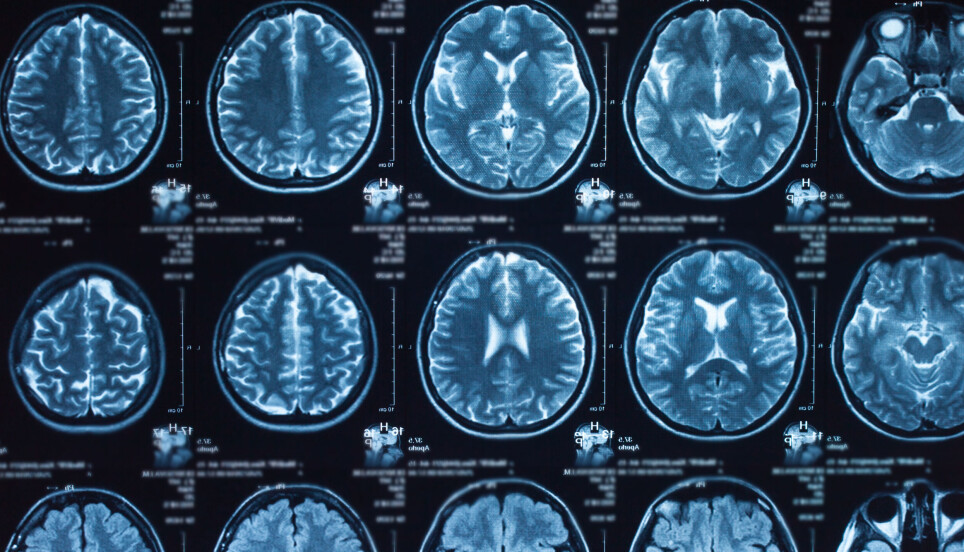

Neuroimaging of the human brain.

"In previous studies, that I referred to earlier, researchers looked at MRI images of the brain of people with schizophrenia. They revealed that people with schizophrenia had some unusual changes in the structure of the brain. This was when the researchers discovered that the thickness and size of the surface of the brain were different from healthy people. However, the researchers were not able to prove the genetic overlap statistically," Weiqiu Cheng explains.